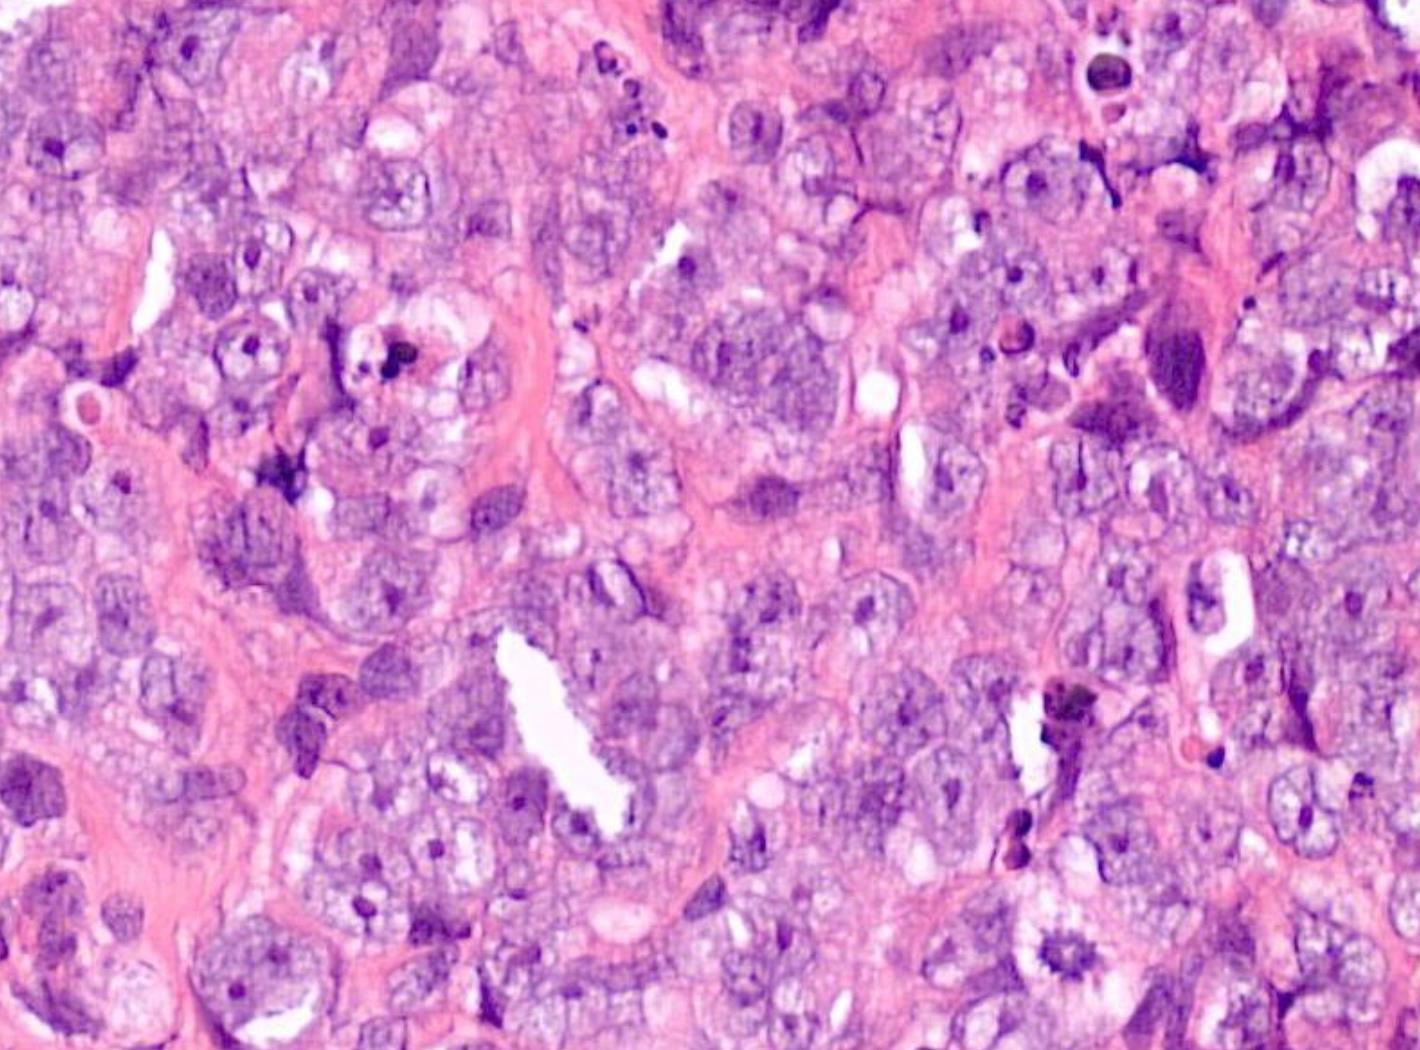

Case 12 55-year-old, Male Lump In Parotid.

??

Case 12 Diagnosis

Acinic cell carcinoma

Notes • Lymphoid

• ACC • MEC • Prognostic factor- better

indicator • ACC can undergo HG transformation

stroma